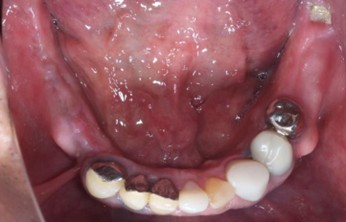

70代 女性

治療前

- 70代/女性

- 患者の具体的な症状

- 下顎の奥歯が義歯で噛みづらいため、インプラント治療を希望

- 検査方法

- コーンビームCT、レントゲン撮影

- 診断結果

- 左下6欠損

- 治療詳細

- 左下6インプラント埋入1本、骨造成なし、局所麻酔

- 通院回数

- 8回

- 治療期間

- 6か月